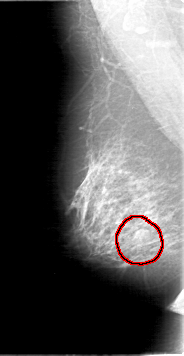

D_4067_1.RIGHT_MLO

FILE: D_4067_1.RIGHT_MLO.OVERLAY

TOTAL_ABNORMALITIES 1

ABNORMALITY 1

LESION_TYPE MASS SHAPE OVAL MARGINS MICROLOBULATED

ASSESSMENT 0

SUBTLETY 4

PATHOLOGY BENIGN

TOTAL_OUTLINES 1

BOUNDARY